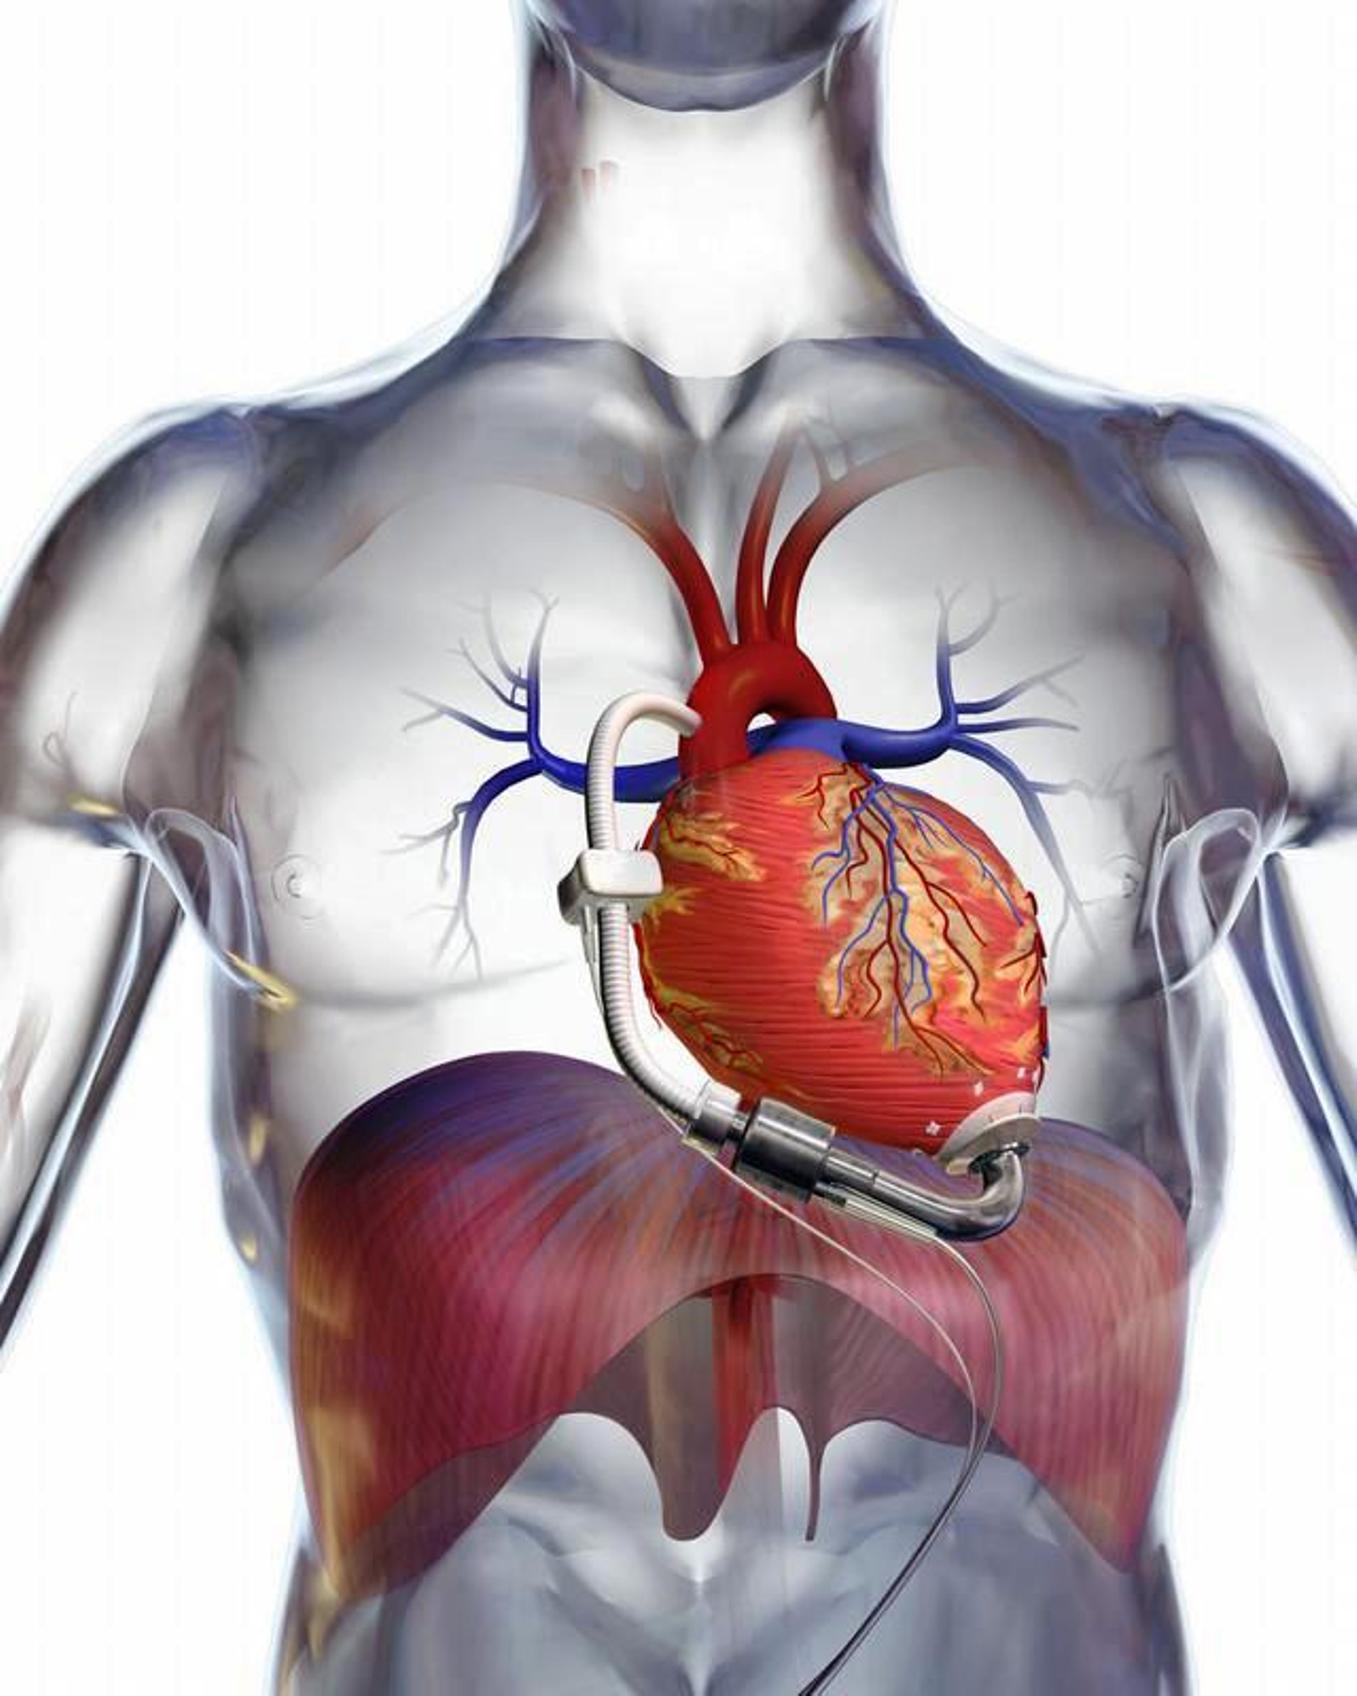

Сердце у человека располагается в грудной полости.

Сердце в грудной клетке расположено.